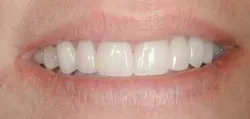

A patient came to my office (fig. 1) with some legitimate esthetic concerns. She had feldspathic porcelain veneers done 16 years ago in an effort to cover dark tetracycline staining. The patient reported being very satisfied with the outcome at the time. However, as time passed, the smile she once felt so good about began to make her feel self-conscious again.

The final result of this case sees an improvement in all of the original objectives (Figs. 12, 13, 14). Our patient wanted a lighter, wider smile that would cover the darkness she had lived with her entire life. Needless to say, she was ecstatic with the end results (Figs. 15, 16).